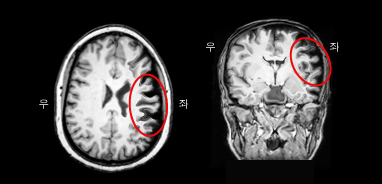

이마관자엽 치매 환자의 MRI. 전두엽이 위축이 두드러짐.

다른 치매와 마찬가지로 신경심리검사를 통하여 치매 여부를 판단하고, 그 아형을 분류한다. 또한 뇌 자기공명영상(뇌 MRI) 및 양성자단층촬영(PET) 등으로 다른 치매와 감별을 시도한다. 이마관자엽변성 환자의 MRI를 보면 이마관자엽치매(FTD)는 전두엽의 위축이 두드러지고, 의미치매는 측두엽의 위축, 그리고 진행성비유창성실어증은 브로카영역의 위축이 뚜렷하다.